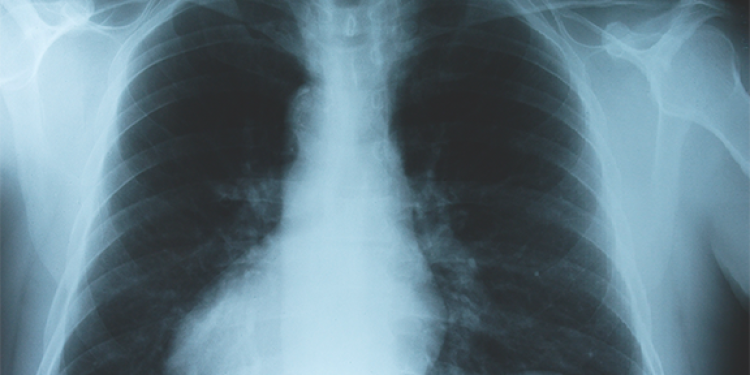

In 2023, the guidelines for lung cancer screening received an important update, making it easier for more patients to qualify for screening. Lung cancer screening usually involves a low dose computed tomography (LDCT) scan. At-risk patients are urged to get screened once a year, and almost all insurance plans and Medicare cover the procedure for those who meet current guidelines.